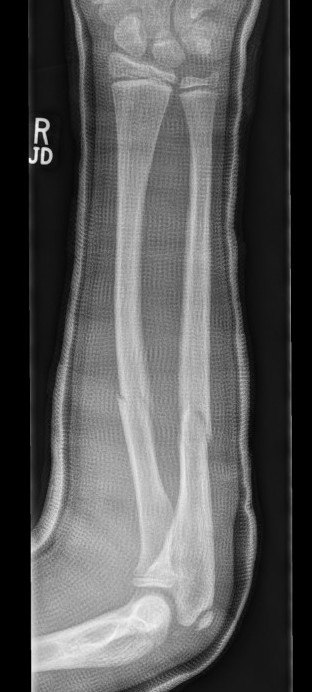

Types

Complete

Greenstick

Buckle / torus

Single or both bone